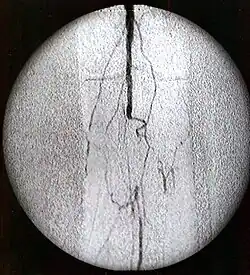

Contrastes radiológicos yodados

Se trata del grupo más importante dentro de los medios de contraste, ya que son los más usados. Se caracterizan por una alta densidad de contraste y una baja toxicidad.

Su estructura química se corresponde con un núcleo benzoico yodado.

Los contrastes yodados se pueden administrar tanto por vía oral, como por vía endovenosa, y dependiendo de la vía de administración, presentaran características farmacocinéticas diferentes.

Los contrastes yodados administrados por vía oral se absorben muy poco y se eliminan fácilmente por vía rectal, mientras que los administrados por vía endovenosa, se eliminan prácticamente de forma total por vía renal, y es solo un 2% excretado por vía biliar.